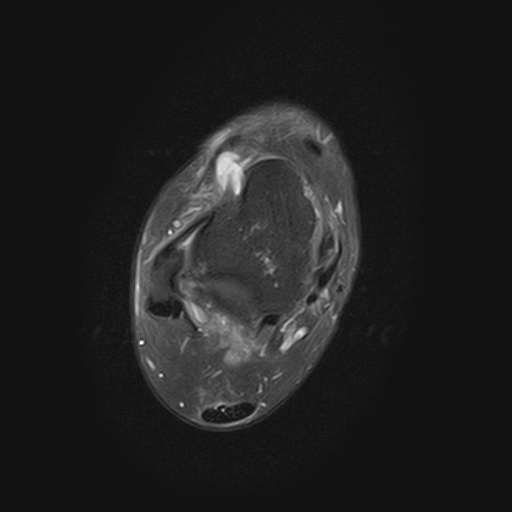

②足関節MRI撮影において、足関節用コイルに腓骨が触れてしまうと感度ムラが起きてしまうため、スポンジを挟み内旋させて対応していました。また、COR・SAG・AX像を撮影する際には脛骨や距骨を基準としていました。そしてATFLに平行なスライスで撮影したところ低信号でした。CFLの走行も踵骨から腓骨付着部まで確認できました。ATFLの信号について、正常例や陳旧性損傷例は低信号、新鮮損傷例は高信号とのことでした。

研修日当日は足関節CT撮影がありませんでしたので、3次元画像解析ワークステーション(SYNAPSE VINCENT,FUJIFILM)を用いて以前検査された足関節CT画像を3D画像にして骨の解剖を勉強しました。ATFLに平行なスライスでMPR画像を作成しましたが、靭帯はうっすらとわかる程度でした。

超音波検査では見ることの難しいCFLの腓骨付着部を確認できたこと、MRI画像上でATFLとCFLの走行を確認できたこと、ATFLを超音波検査する際にランドマークとなる距骨滑車と距骨頚部を3D画像上で確認できたことを、今後の検査に生かしていきたいです。